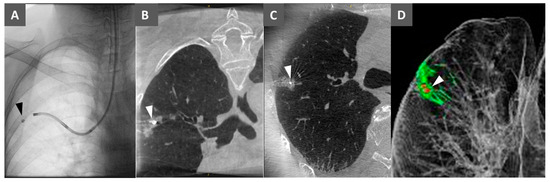

2.3. Virtual Bronchoscopic Navigation

2.4. Bronchoscopic Metallic Coil Marking Procedure